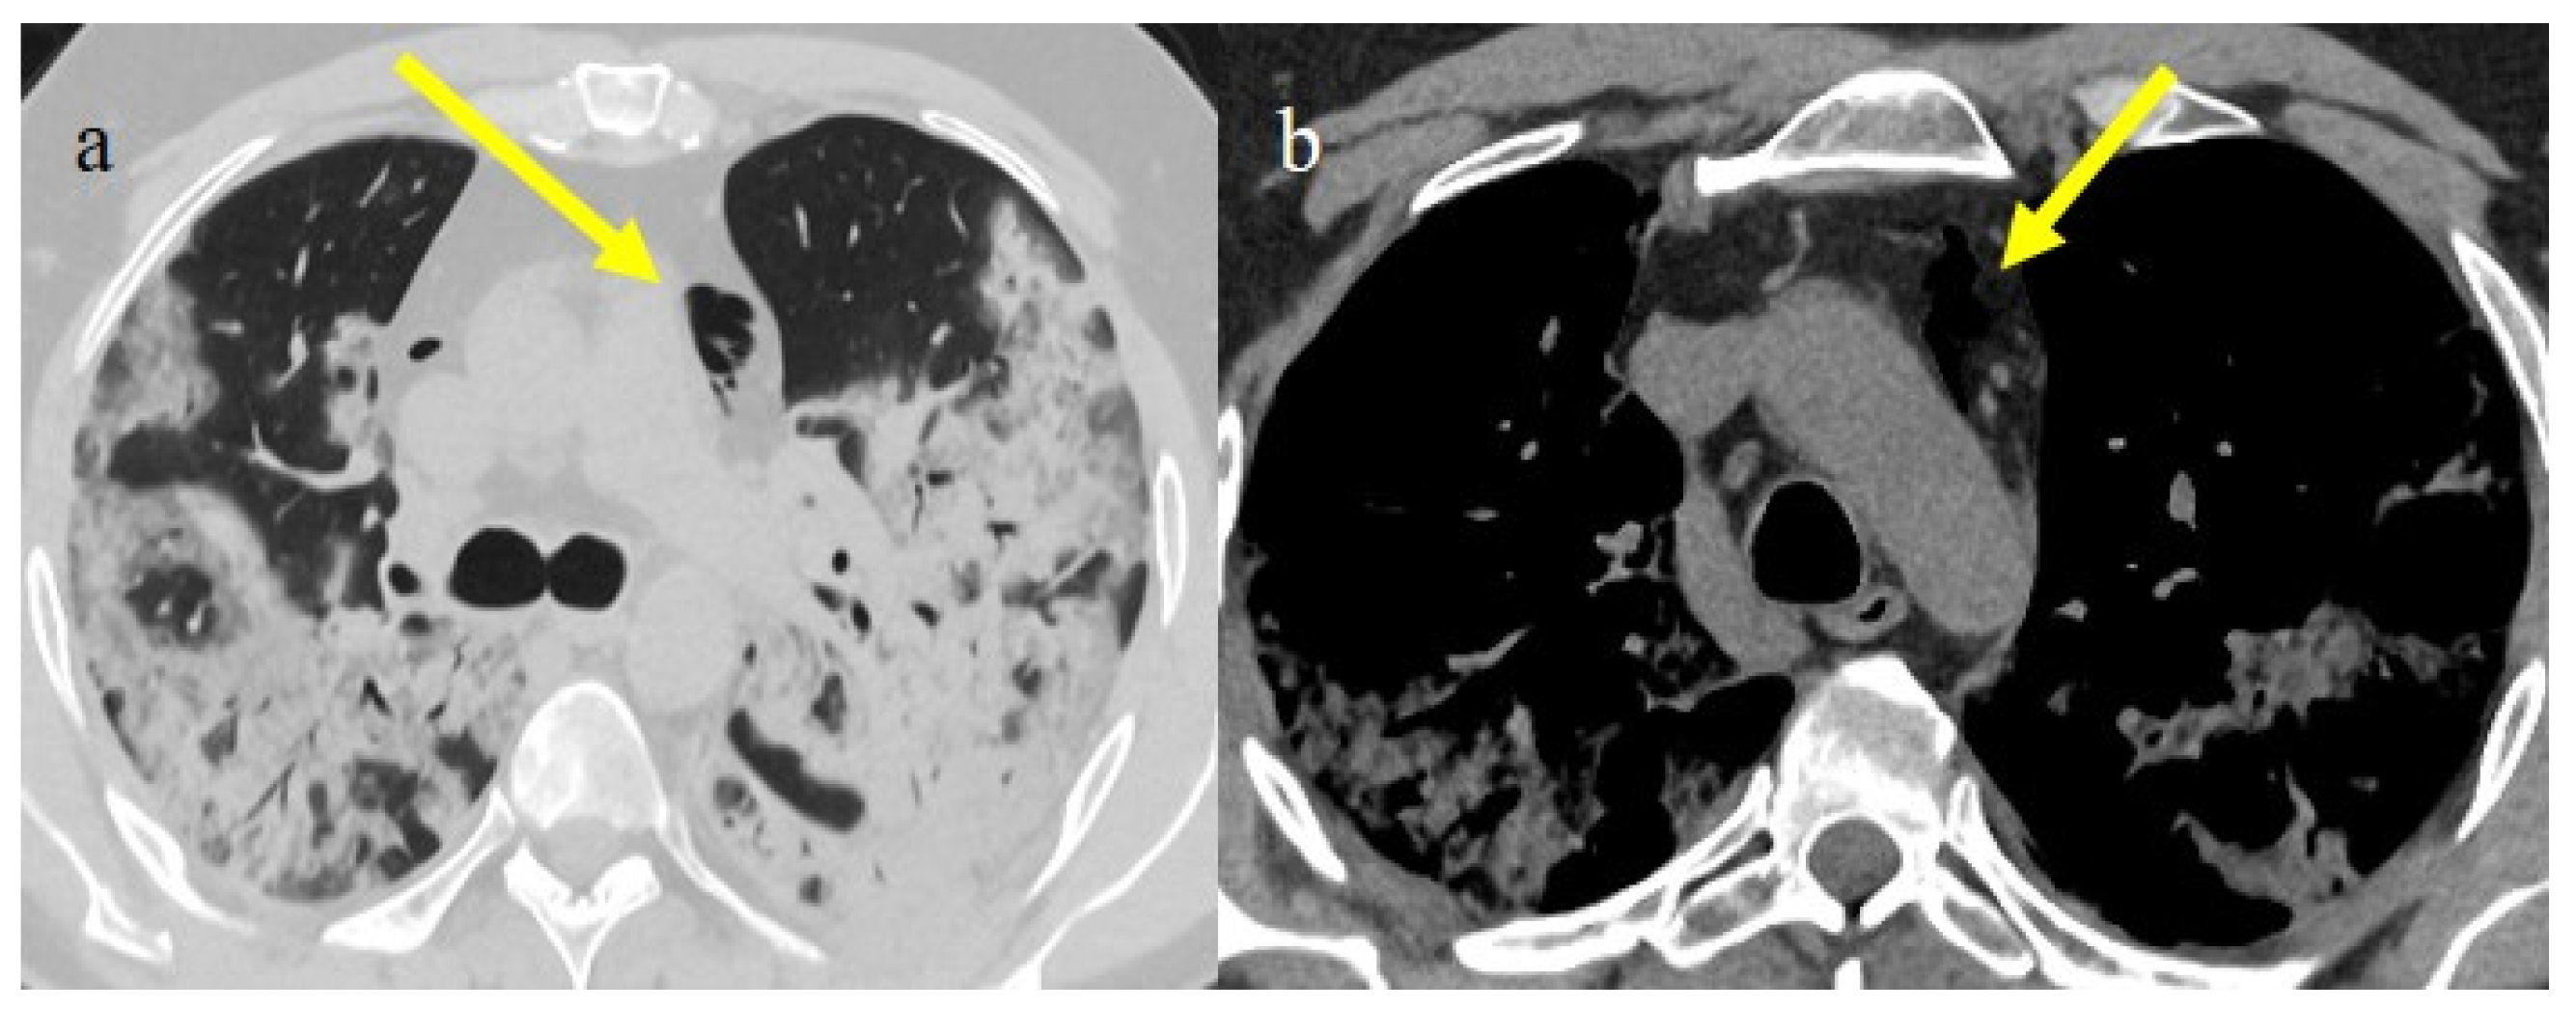

4.1. Small Bowel Ischemia and Ischemic Colitis

4.2. Splenic and Renal Infarction

- Bonaffini, P.A.; Franco, P.N.; Bonanomi, A.; Giaccherini, C.; Valle, C.; Marra, P.; Norsa, L.; Marchetti, M.; Falanga, A.; Sironi, S. Ischemic and hemorrhagic abdominal complications in COVID-19 patients: Experience from the first Italian wave. Eur. J. Med. Res. 2022, 27, 1–9. [Google Scholar] [CrossRef]

- Peshevska-Sekulovska, M.; Boeva, I.; Sekulovski, M.; Zashev, M.; Peruhova, M. Gastrointestinal Ischemia—Stumbling Stone in COVID-19 Patients. Gastroenterol. Insights 2022, 13, 206–217. [Google Scholar] [CrossRef]

- Norsa, L.; Bonaffini, P.A.; Caldato, M.; Bonifacio, C.; Sonzogni, A.; Indriolo, A.; Valle, C.; Furfaro, F.; Bonanomi, A.; Franco, P.N.; et al. Intestinal ischemic manifestations of SARS-CoV-2: Results from the ABDOCOVID multicentre study. World J. Gastroenterol. 2021, 27, 5448–5459. [Google Scholar] [CrossRef]

- Castro, G.R.A.; Collaço, I.A.; Bosco, C.L.B.D.; Corrêa, G.G.; Bosco, G.B.D.; Corrêa, G.L. Splenic infarction as a complication of covid-19 in a patient without respiratory symptoms: A case report and literature review. IDCases 2021, 24, e01062. [Google Scholar] [CrossRef] [PubMed]

- Prentice, G.; Wilson, S.; Coupland, A.; Bicknell, S. Complete splenic infarction in association with COVID-19. BMJ Case Rep. 2021, 14, e246274. [Google Scholar] [CrossRef] [PubMed]

- Post, A.; den Deurwaarder, E.S.G.; Bakker, S.J.L.; de Haas, R.J.; van Meurs, M.; Gansevoort, R.T.; Berger, S.P. Kidney Infarction in Patients with COVID-19. Am. J. Kidney Dis. 2020, 76, 431–435. [Google Scholar] [CrossRef]

- Al-Mashdali, A.F.; Alwarqi, A.F.; Elawad, S.M. Simultaneous renal infarction and splenic infarction as a possible initial manifestation of COVID-19: A case report. Clin. Case Rep. 2021, 9, 4819. [Google Scholar] [CrossRef]

- Brem, F.L.; Abu Al Tayef, T.; Rasras, H.; El Mahi, O.; El Ouafi, N.; Zakaria, B. Concomitant renal and splenic infarctions in a COVID-19-patient with a catastrophic thrombotic syndrome. Radiol. Case Rep. 2022, 17, 4030–4033. [Google Scholar] [CrossRef]

- Ramanathan, M.; Chueng, T.; Fernandez, E.; Gonzales-Zamora, J. Concomitant renal and splenic infarction as a complication of COVID-19: A case report and literature review. Infez. Med. 2020, 28, 611–615. [Google Scholar]

- Mavraganis, G.; Ioannou, S.; Kallianos, A.; Rentziou, G.; Trakada, G. A COVID-19 Patient with Simultaneous Renal Infarct, Splenic Infarct and Aortic Thrombosis during the Severe Disease. Healthcare 2022, 10, 150. [Google Scholar] [CrossRef]